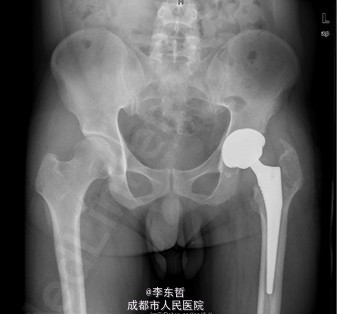

患者男,31岁,因“左股骨头股骨颈骨折切开复位内固定术后1+年”入院。患者1+年前因车祸致左股骨头、颈粉碎性骨折伴坐骨神经损伤于我院就诊,于我院行左股骨头股骨颈骨折切开复位空心钉+可吸收镙钉内固定术,术后恢复良好出院。术后8月后扶双拐活动。7月前患者无明显诱因出现左髋部疼痛,以负重时为重,后患者只能扶双拐活动。现患者为进一步治疗入我院。患病以来患者精神可,食欲可,睡眠可,大小便未见明显异常,体重无明显变化。

查体:T:36.2oC,P:80次/分,R:20次/分,BP:112/74mmHg。神志清楚,无病容,皮肤巩膜无黄染,全身浅表淋巴结未见肿大。颈静脉搏动、心界正常,心律齐,各瓣膜区未闻及杂音。胸廓未见异常,双肺叩诊呈清音,双肺呼吸音清,未闻及干湿啰音及胸膜摩擦音。腹部外形正常,全腹柔软,无压痛及反跳痛,腹部未触及包块,肝脏肋下未触及,脾脏肋下未触及,双肾未触及。双下肢无水肿。视:左髋外侧可见一约30cm手术瘢痕,其上可见一点状结痂,左腿较右腿短缩,左腿肌肉较右腿萎缩,步态异常。触:左髋部无压痛,左腿外侧感觉异常,以左膝外侧为重,左髋外侧叩击痛,左足背动脉搏动未扪及异常。动量:左下肢较右下肢短缩约3cm,左髋关节活动受限,其余各关节未见明显异常。

入院诊断:左股骨头股骨颈粉碎性骨折切开复位内固定术后坏死;积极完善术前检查及准备后行关节置换术。